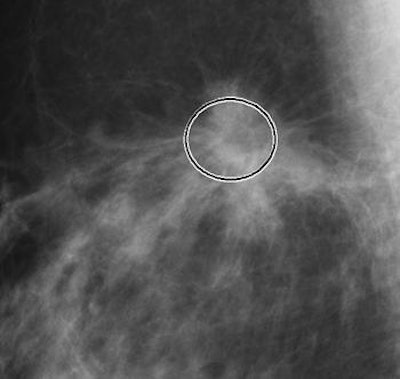

| Microcalcifications (above) within the rectangular frames show the extent the calcifications that are detected by CAD. Masses (below), architectural distortions, and focal asymmetries are marked with the circular frame. Images courtesy of iCAD. |